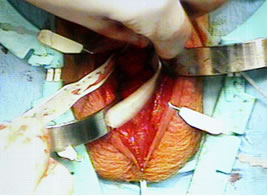

Произведена сборка и заполнение коннекторных трубочек и частей сфинктера физиологическим раствором. На уретру с помощью фиксирующего окна установлена манжетка (4,0см).Пальпаторно определено наружное паховое кольцо справа. Ножницами рассечена поперечная фасция, послеоперационные спайки. Окно расширено пальцем и в паравезикальное пространство справа имплантирован баллон сфинктера.Баллон наполнен 22мл физиологического раствора. Клапан сфинктера имплантирован в мошонку. Соединяющие трубки укорочены таким образом, чтобы они не провисали и не перегибались. Коннекторные трубки герметично соединены посредством замков, которые фиксируются между собой специальным инструментом. Выполнен антибактериальный лаваж. Дренирование раны не выполнялось. Ушивание раны. Асептическая наклейка.

Основные этапы операции.